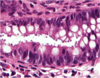

What is this?

cryptosporidosis

C. parvum infection

What is this?

cryptosporidosis

C. parvum infection

on Kinyoun acid fast stain